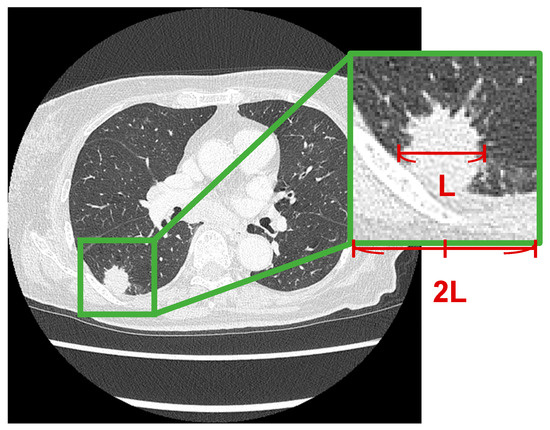

Preliminary Study on Image-Finding Generation and Classification of Lung Nodules in Chest CT Images Using Vision–Language Models

Computers 2025, 14(11), 489; https://doi.org/10.3390/computers14110489 - 9 Nov 2025

In the diagnosis of lung cancer, imaging findings of lung nodules are essential for benign and malignant classifications. Although numerous studies have investigated the classification of lung nodules, no method has been proposed for obtaining detailed imaging findings. This study aimed to develop

In the diagnosis of lung cancer, imaging findings of lung nodules are essential for benign and malignant classifications. Although numerous studies have investigated the classification of lung nodules, no method has been proposed for obtaining detailed imaging findings. This study aimed to develop a novel method for generating image findings and classifying benign and malignant nodules in chest computed tomography (CT) images using vision–language models. In this study, we collected chest CT images of 77 patients diagnosed with either benign or malignant tumors at Fujita Health University Hospital. For these images, we cropped the regions of interest around the nodules, and a pulmonologist provided the corresponding image findings. We used vision–language models for image captioning to generate image findings. The findings generated by these two models were grammatically correct, with no deviations in notation, as expected from the image findings. Moreover, the descriptions of benign and malignant characteristics were accurately obtained. The bootstrapping language–image pretraining (BLIP) base model achieved an accuracy of 79.2% in classifying nodules, and the bilingual evaluation understudy-4 score for agreement with physician findings was 0.561. These results suggest that the proposed method may be effective for classifying and generating lung nodule findings.